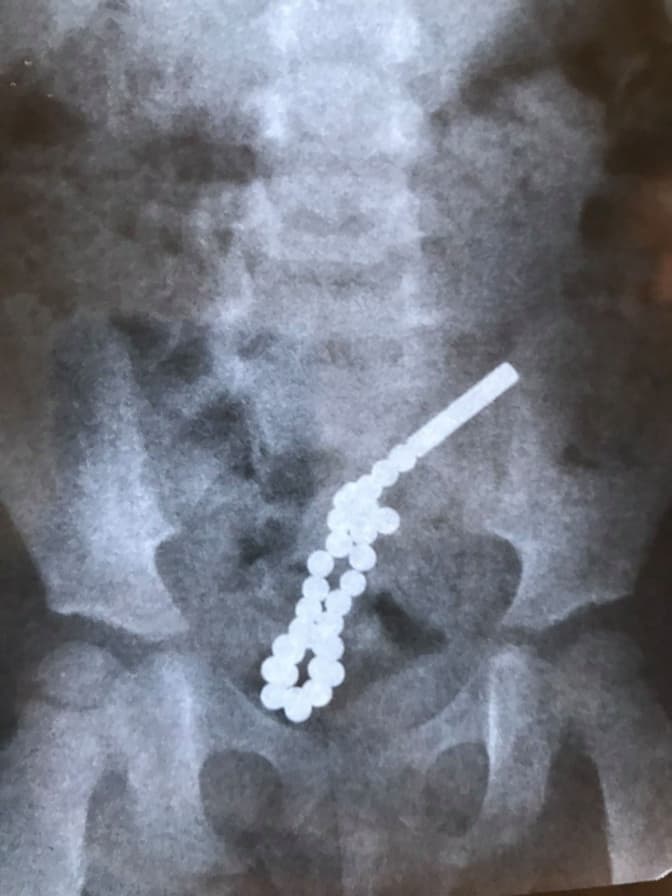

У Дитячій лікарні на Пилипа Орлика прооперували дворічну дівчинку, яка проковтнула 31 неодимовий магніт.

«Ці магніти настільки потужні, що у кишківнику через стінку кишки між собою склеїлися і утворилося 7 перфоративних отворів, тобто 7 дірок. Дитині спочатку зробили колоноскопію, під час якої і виявили, що вже є перфоративний отвір з товстого кишківника у тонкий. Довелося оперувати», – розповів лікар-хірург відділення хірургії вроджених вад розвитку Дмитро Грицак.